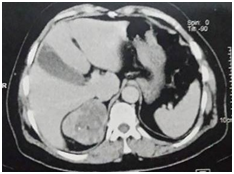

A CT scan showed a right lesional adrenal process, well confined by lobulated contours, hypodense, containing greasy spots and calcifications (Figure 1), heterogeneously enhanced after a contrastive injection (Figure 2), measuring 71×60×55mm.

Figure 2 Scanner showing adrenal mass heterogeneously enhaced after contrast injection and containing calcifications.

Frontwards, this process comes in contact with the inferior vena cava and segment VII of the liver without signs of invasion. Internally, he contacts the diaphragm’s pillar with the loss of separation greasy edges in some place. The radiological aspect is highly suggestive of malignant adrenal tumor.